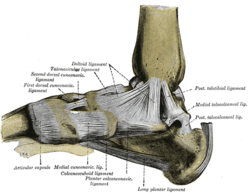

Ligaments of the medial aspect of the foot. (Calcaneocuboid labeled at bottom center.) | |

Ligaments

The ligaments connecting the calcaneus with the cuboid are five in number, viz., the articular capsule:

- the dorsal calcaneocuboid ligament,

- part of the bifurcated ligament,

- the long plantar ligament,

- and the plantar calcaneocuboid ligament.